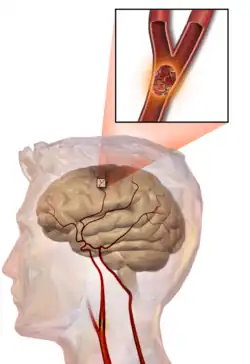

Illustration of an embolic stroke, showing a blockage lodged in a blood vessel

In thrombotic stroke, a thrombus[47] (blood clot) usually forms around atherosclerotic plaques. Since blockage of the artery is gradual, onset of symptomatic thrombotic stroke is slower than that of hemorrhagic stroke. A thrombus itself (even if it does not completely block the blood vessel) can lead to an embolic stroke (see below) if the thrombus breaks off and travels in the bloodstream, at which point it is called an embolus. Two types of thrombosis can cause stroke: